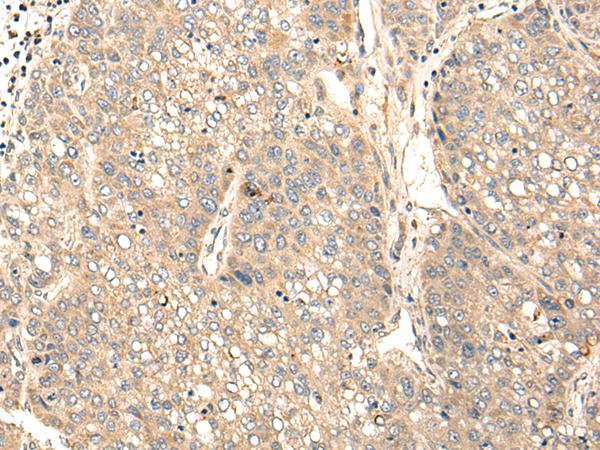

IHC positive control: |

Human liver cancer and human esophagus cancer |

IHC Recommend dilution: |

25-100 |